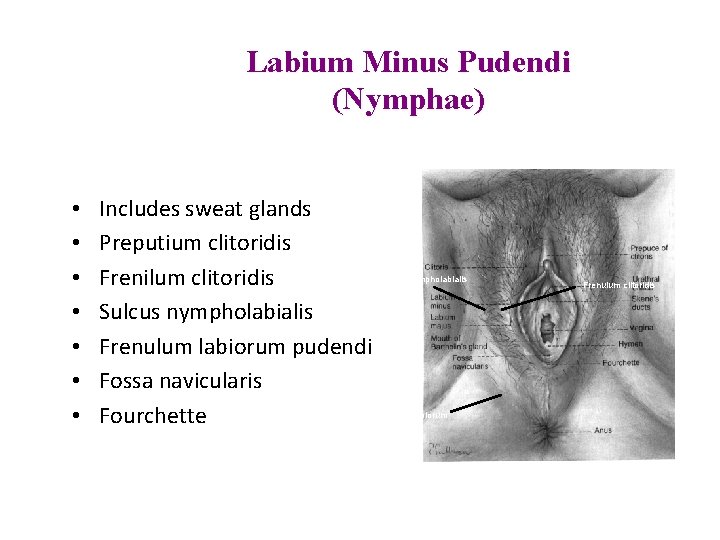

Labium Minus Pudendi (Nymphae) • • Includes sweat glands Preputium clitoridis Frenilum clitoridis Sulcus nympholabialis Frenulum labiorum pudendi Fossa navicularis Fourchette Sulcus nympholabialis Frenulum labiorum pudendi Frenulum clitoridis